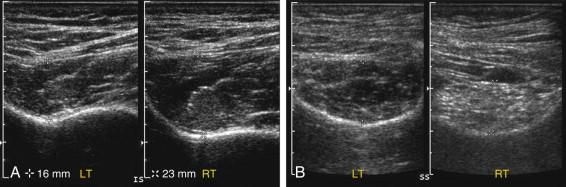

Muscle atrophy can also be detected and quantified sonographically. Comparison of the right and left sides is easy using dual-screen acquisition ( Fig. 11-17A ). Fatty infiltration is also detectable by noting increased muscle echogenicity. This is an important part of evaluation of the shoulder in patients with rotator cuff tears (see Fig. 11-17B ).

F igure 11-17, Muscle atrophy in different patients with rotator cuff tears. A, Dual views of the left (LT) and right (RT) infraspinatus muscles show symmetric echogenicity of the muscles, but decreased thickness of the left compared with the right (16 mm vs. 23 mm) indicating atrophy. B, Dual views of the left and right supraspinatus muscles show increased echogenicity and decreased thickness of the right muscle indicating atrophy and fatty infiltration.